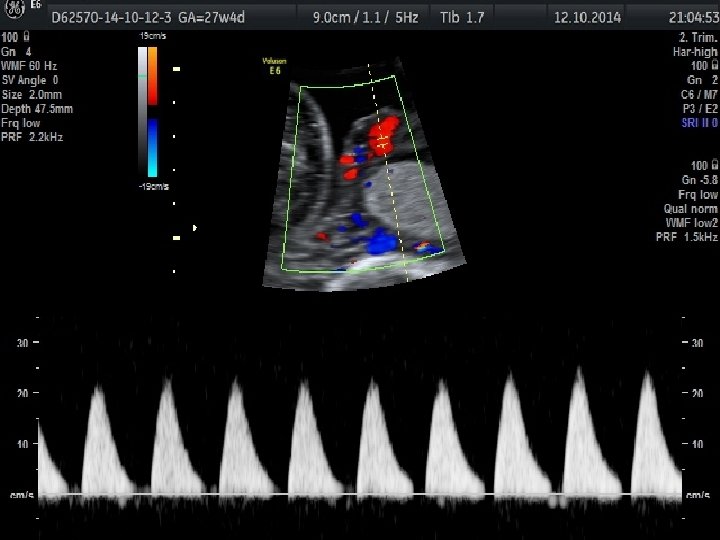

Obstetrik Doppler Ultrasonografi • Umblikal arter Doppler’i en yaygın olarak kullanılan fetal Doppler değerlendirmesidir ve en fazla kullanılan Doppler parametresidir. • Orta serberal arter Doppler • Umblikal arter Doppler değerlendirmesinde direnç artışı, diyastol sonu akımda kayıp veya ters dönme saptanması , artmış perinatal mortalite hızı ile ilişkili olmakla birlikte fetal gelişme geriliği olgularında doğum zamanlamasının belirlenmesini de etkilemektedir.

• Duktus venosus Doppler’inin kötü perinatal sonuçları tahmin etmedeki katkısı sınırlı olmakla birlikte yenidoğan sonuçlarını öngörmede en önemli kardiyovasküler parametre duktus venosus Doppler’idir.

Eğer akım transdu sere doğru ise, yol uzunluğu kısadır ve geri dönen frekans yu ksektir. Eğer akım transdu serden uzaklaşıyorsa, yol uzar ve geri dönen frekans azalır.